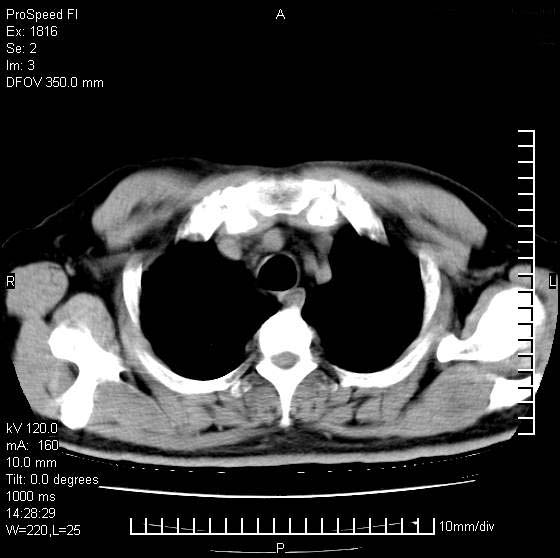

男性,50 ,肺结核9年,咳嗽,胸痛一周。右上肺见一厚壁空洞,周边有点样钙化,胸膜牵拉,洞壁较光整。诊断结核性空洞。有癌性的可能吗? 余肺野无异常,没有上传。

洞壁较厚内壁比较光整,两个病灶有关联性,纵隔淋巴结不大,考虑结核性空洞。

右肺上叶为两个病灶,前面为陈旧型结核灶,其后方病灶像肺脓肿

9年的结核应该呈现多形态病灶,该病例只能见到少许纤维索条影,似乎与结核的演变不太相符。空洞内壁不光整,外侧伴有胸膜粘连,考虑癌性空洞可能性大,期待结果。

壁较厚内壁比较光整,两个病灶有关联性,纵隔淋巴结不大,考虑结核性空洞